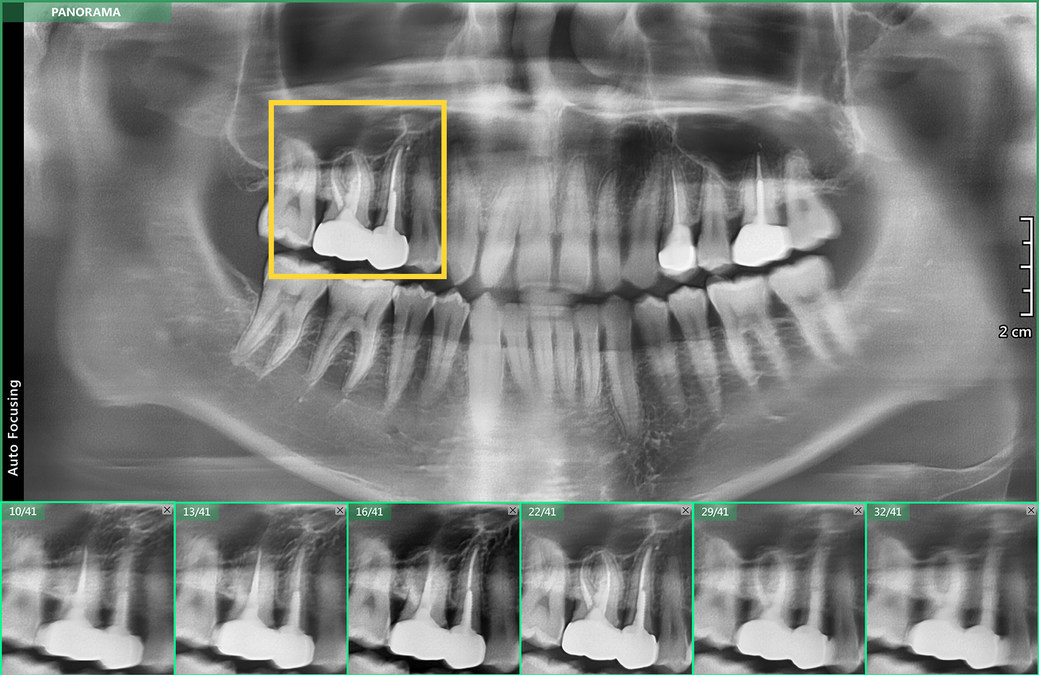

Images from the analysis are transmitted to a camera or video system and can be helpful for both the professional and client. Therefore extraoral dental radiographies such as panoramic radiography and cone beam computed tomography CBCT are appropriate alternatives during the outbreak of COVID-19. ELlNT is used to identify the location of an emitter determine its characteristics and infer the characteristics of supported systems.

They are used in both projectional radiography and as an alternative to x-ray image intensifiers IIs in fluoroscopy equipment. Panoramic X-rays are used to plan treatment for dental implants detect impacted wisdom teeth and jaw problems and diagnose bony tumors and cysts. Toggle navigation NGS Home.

For all cases requiring intervention the provider should obtain pre- and post-procedural imaging. CBCT imaging surpassed the obstacles of 2D imaging offering practitioners with high quality sub-millimeter resolution images with short scanning time and low radiation dose. Videos may also be used.

Panoramic imaging is helpful to visualize the dentition and also should be assessed for mandibular fractures.